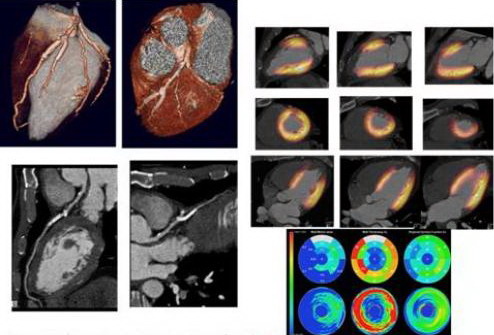

Ghi hình PET trong bệnh Alzheimer (hình ảnh giảm chuyển hóa) Các ứng dụng của PET và PET/CT trong tim mạch học là ghi hình tưới máu cơ tim và đánh giá sự sống còn của cơ tim. Ghi hình tưới máu cơ tim với PET có độ nhạy lớn hơn ít nhưng độ đặc hiệu lớn hơn đáng kể so với kỹ thuật SPECT. FDG-PET đối với đánh giá sự sống còn của cơ tim làm tăng tỷ lệ phần trăm biểu hiện bệnh lý cơ tim về chứng thiếu máu cục bộ hoặc đánh giá sau ghép tim. FDG-PET cũng được chấp nhận rộng rãi là một tiêu chuẩn vàng đối với đánh giá sự sống còn của cơ tim...

Bệnh nhân bị nhồi máu cơ tim trước vách và được đặt stent cấp cứu ở nhánh chéo đầu tiên ở động mạch xuống trước trái. Chụp mạch cho thấy dòng chảy phía sau stent bình thường. FDG PET cho thấy không có dấu hiệu cơ tim còn sống ở vách tim ngoại vi do nhồi máu cơ tim cũ. Phân tích độ dày và chuyển động của vách tim trên cửa sổ CT cho thấy vách cơ tim mỏng và giảm vận động của vách trước